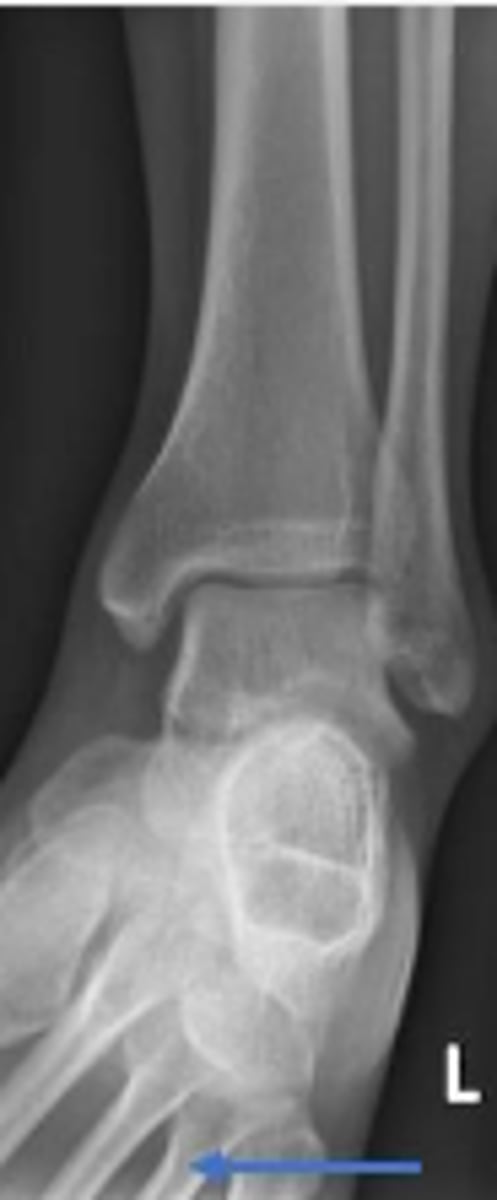

Left internal oblique ankle

What is the name of the radiographic view?

Left fibula

What bone are the arrows pointing t

4th metatarsal